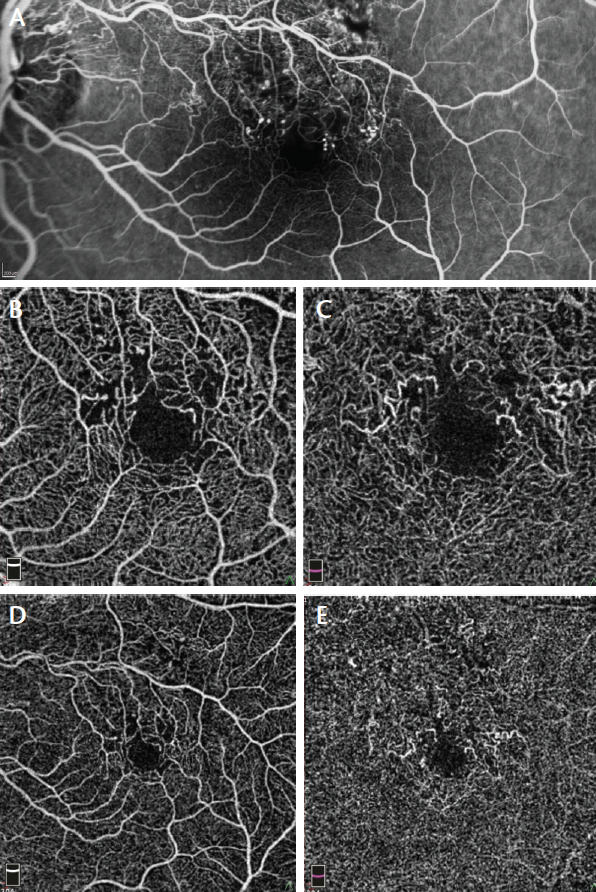

Case Example

Figure 6. FA (A) and 3 mm x 3 mm (B) and 6 mm x 6 mm (D) superficial plexus OCTA of a 47-year-old man with ischemic BRVO show rarefaction of capillary texture, microaneurysms, and capillary dropout. By contrast, 3 mm x 3 mm (C) and 6 mm x 6 mm (E) deep plexus OCTA show capillary dilation and vessel congestion, probably due to high hydrostatic pressure. These features are not visible on FA.

We performed FA (Figure 6A) and OCTA of the superficial plexus (Figure 6B and 6D) in a 47-year-old man with ischemic BRVO. Both imaging modalities showed rarefaction of capillary texture, microaneurysms, and capillary dropout. OCTA of the deep plexus (Figure 6C and 6E) showed capillary dilation and vessel congestion, likely due to high hydrostatic pressure. These features were not visible on FA.